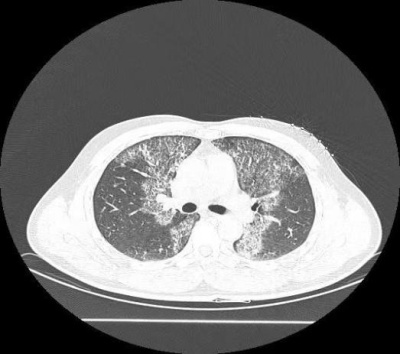

病例一:患者陈新,男,35岁,工人,因“发现肺部阴影1.5月,气短加重10天”入院。患者4天前体检发现肺部阴影,肺CT提示双肺纹理增多、紊乱,双肺多发片状模糊影,考虑感染性病变。患者自述活动后胸闷、气短,休息可缓解,曾规律口服醋酸泼尼松片(剂量递减),但已自行停药1周。入院后复查肺部CT显示右肺下叶实性结节(最大截面约19 mm × 13 mm,边缘毛糙),双肺间质性炎症。支气管镜检见气管及支气管黏膜光滑,管腔通畅,但右中叶内侧段可见白色粘稠分泌物,肺泡灌洗液送检。镜下可见肺泡腔内充满粉染、颗粒状蛋白性物质,其内可见泡沫细胞。

入院评估与初步检查:① 入院后完善肺CT检查,结果显示双肺纹理增多、紊乱,双肺多发片状模糊影,提示感染性病变;复查CT发现右肺下叶实性结节双肺间质性炎症。② 行支气管镜检查:观察气管及支气管黏膜光滑,管腔通畅,但右中叶内侧段可见白色粘稠分泌物,于右中叶内侧段行肺泡灌洗,使用生理盐水100 ml,回收65 ml灌洗液,留样送检。③ 病理诊断与特殊染色:标本经病理检查镜下可见肺泡腔内充满粉染、颗粒状蛋白性物质,其内可见泡沫细胞。④ 肺泡灌洗液标本特殊染色结果:AB-PAS (爱先蓝–糖原)染色及PAS (糖原)染色均呈阳性,提示肺泡腔内沉积物为蛋白性物质。⑤ 结合临床及影像学表现,诊断为肺泡蛋白沉积症(PAP)。最终结合临床考虑肺泡蛋白沉积症(PAP)。